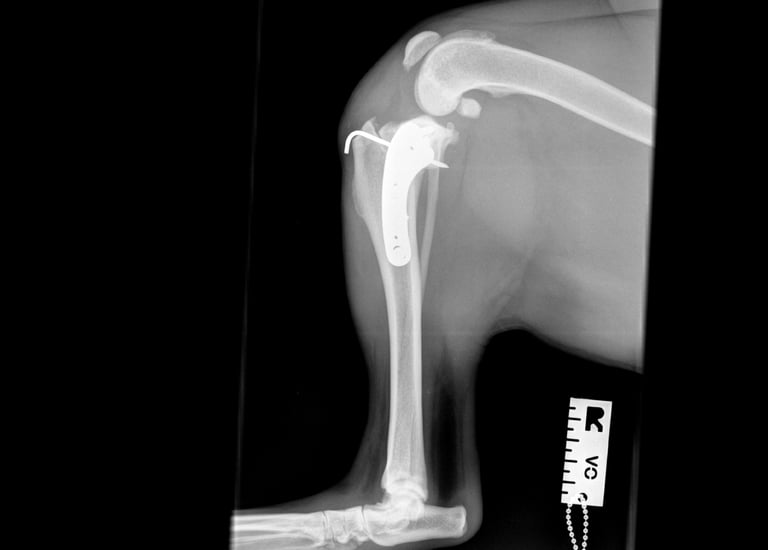

Postoperative radiographs showed that the proximal screw of the distal fragment is slightly longer than expected, but this is not anticipated to cause clinical issues. GImplants are in good position, there is correct compression and alignment is also optimal.

Postoperative TPA measured at 4.3°.

At the first postoperative recheck (day 3), Luna was nearly fully weight-bearing with only mild lameness. The surgical site showed excellent healing and 6 weeks post-op xrays (Figs. 7 and 8) show good ossification of osteotomy line and good position of implants.

Fig. 7

Fig. 8